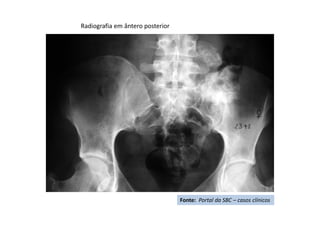

RX da coluna torácica -

Perfil

Fonte: Portal da SBC – casos clínicos

RM - corte sagital de

imagem ponderada em T2

com supressão de gordura

imagem ponderada em

T2

RM - corte axial imagem ponderada em T2

RX – Pós-operatório 4 meses